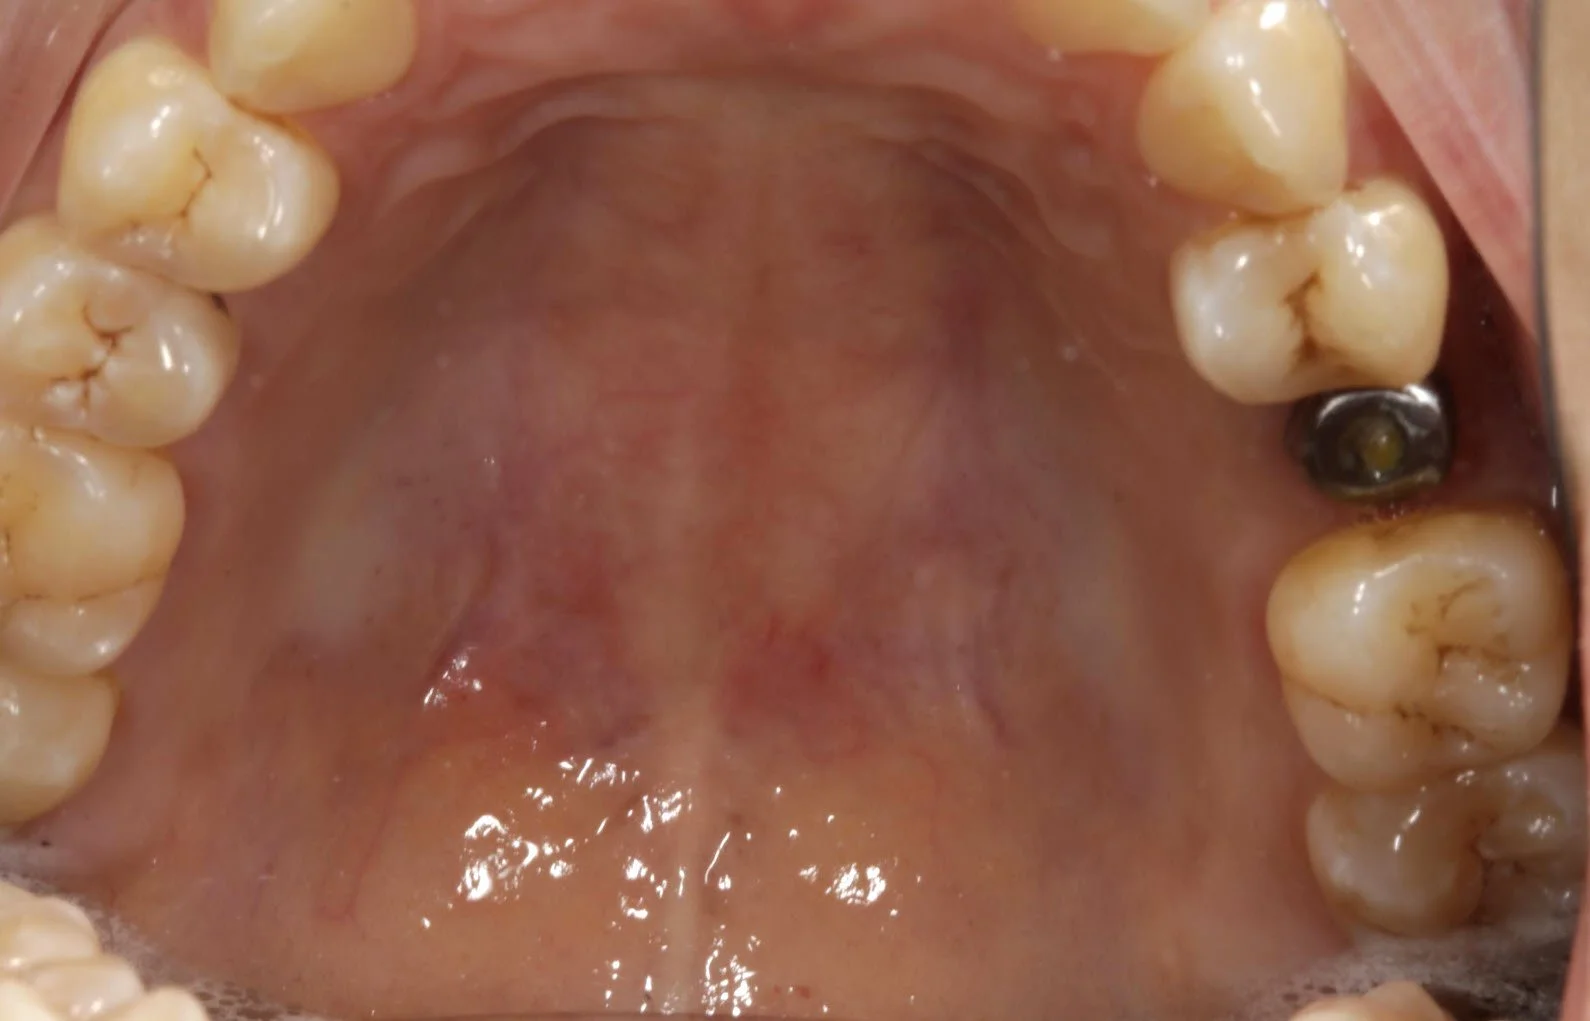

Implant

Before